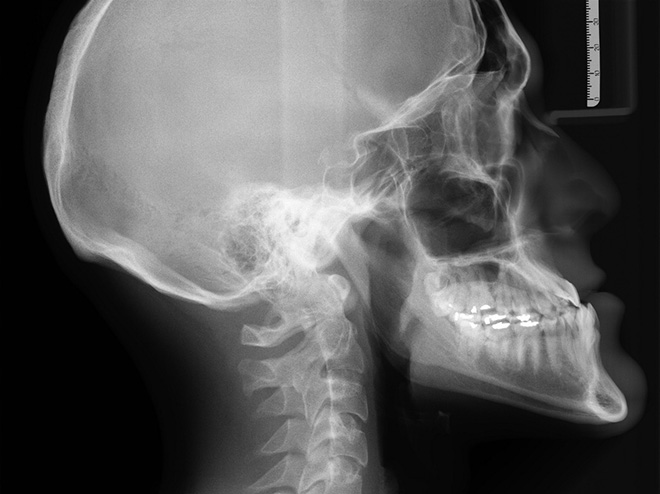

뢴트겐의 놀라운 발견으로 인류는 의학 분야의 큰 발전을 이룰 수 있었고, 의학뿐만 아니라 재료 연구나 여러 검사의 영역에서도 여전히 활발히 쓰이고 있습니다. 뢴트겐이 발견한 것은 바로 X선(X-ray), 병원에서 우리 몸의 안쪽을 들여다보아야 하거나 공항에서 짐 수색이 필요할 때 이 X선이 활용됩니다.

X선은 발견되자마자 많은 분야에서 활용되었는데요. 최초로 X선을 활용하여 절개 없이 골절을 진단하거나, 머리에 박힌 탄환을 확인하기도 하였습니다. 이전에는 신체 내부의 상태를 확인하기 위해 외과적 수술이 필수였는데, X선의 발견으로 절개하지 않고도 이를 확인할 수 있게 된 것입니다. 의학계에서는 페니실린의 발견에 버금가는 혹은 그 이상의 발견이었다고 할 수 있었지요.